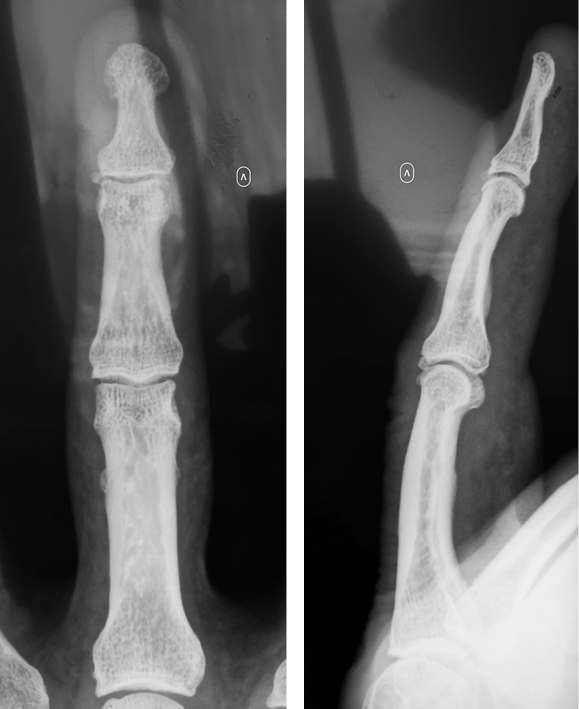

X-ray in two views (in three, if necessary) was performed in both groups of patients. Four (6.4%) patients underwent multiple view radiography to detect an osteophyte. As a result, all patients showed signs of osteoarthritis of the affected joint, and single (36 (58%)) or multiple (22 (35.4%)) osteophytes were detected (Figs. 3, 4). In addition, 48 (77.4%) patients had multiple osteoarthritis of the finger joints (interphalangeal and metacarpophalangeal), 32 (51.6%) had rhizarthrosis, and 46 (74.1%) had signs of wrist osteoarthritis.

Fig. 3. Mucous cyst of the III finger, recurrence after the surgery performed prior to the referral to our clinic

Fig. 4. X-ray of the III finger in the AP (osteophyte of the nail phalanx is visible) and lateral views; recurrence after the surgery performed prior to the referral to our clinic